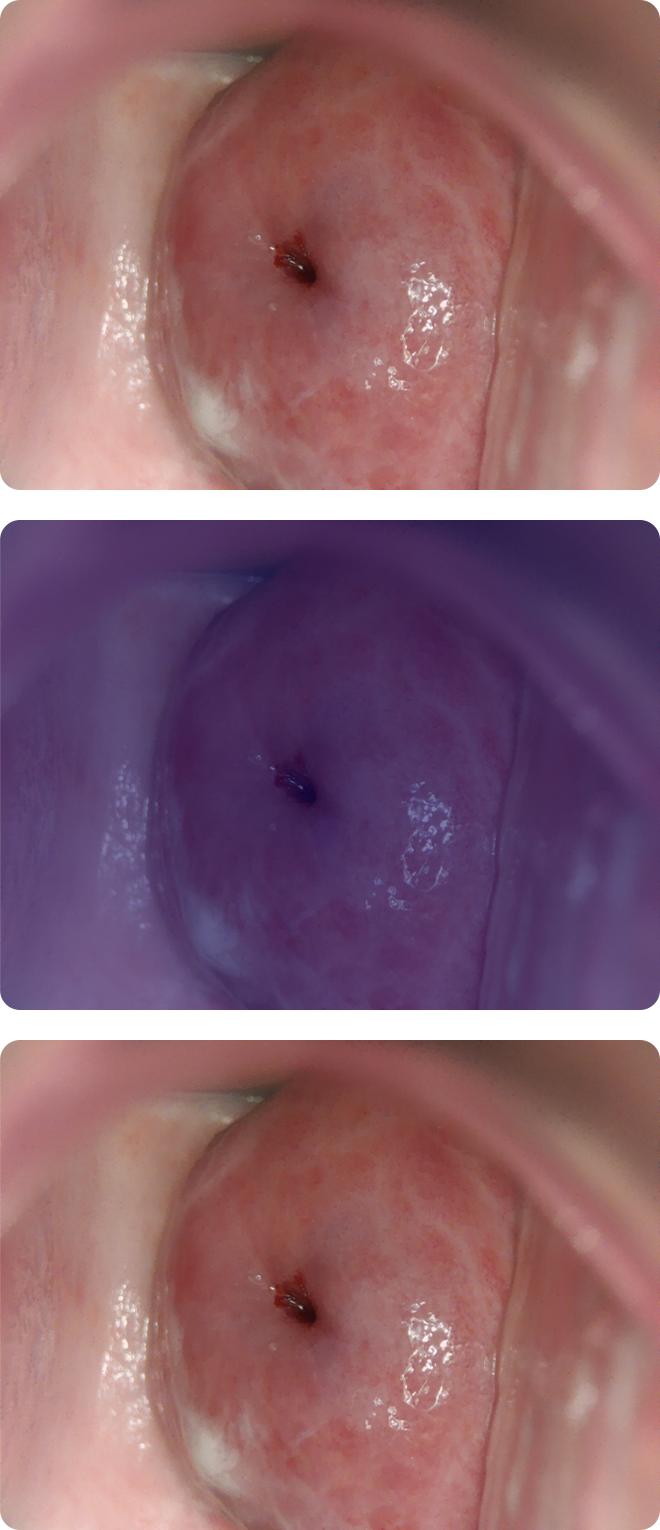

Cerviray AI

Normal